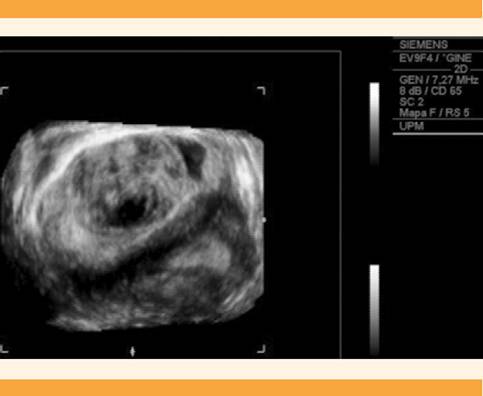

Después de algunos meses acudió, nuevamente, a consulta médica, indicando un incremento significativo de los síntomas, entre los que destacaron importantes molestias vaginales, metrorragias mayores al ciclo menstrual y dispareunia, por lo que se decidió repetir el estudio ecográfico (Figura 1y2) y complementarlo con resonancia magnética para mayor definición. La tumoración aumentó notoriamente de tamaño (58 x 57 x 60 mm), con forma redondeada y aspecto sólido, zonas de hiperseñal en su espesor, quizá por la coexistencia de estructuras venosas y áreas de degeneración mixoide. No se identificaron otros cambios que sugirieran malignidad. La tumoración se encontraba en el espacio vesicovaginal, al parecer dependiente de la pared anterior vaginal, aislada del cuello uterino y del útero, pero sugerente de compresión de la pared posterior de la vejiga urinaria (Figura 3). Con estos datos se estableció el diagnóstico de leiomioma vaginal pediculado. Debido a los signos y síntomas se inició el tratamiento con acetato de ulipristal (5 mg al día) para disminuir el volumen y sangrado miomatoso. Después de dos ciclos de tratamiento la tumoración se incrementó a 70 x 55 mm, por lo que se solicitó la participación multidisciplinaria del servicio de Urología y en común acuerdo se decidió la miomectomía por vía vaginal, esta vez con consentimiento de la paciente.

Figura 1 Ecografía transvaginal de una masa redondeada y homogénea, de 60 x 46 x 48 mm, en la cara anterior de la vagina, de aspecto miomatoso.